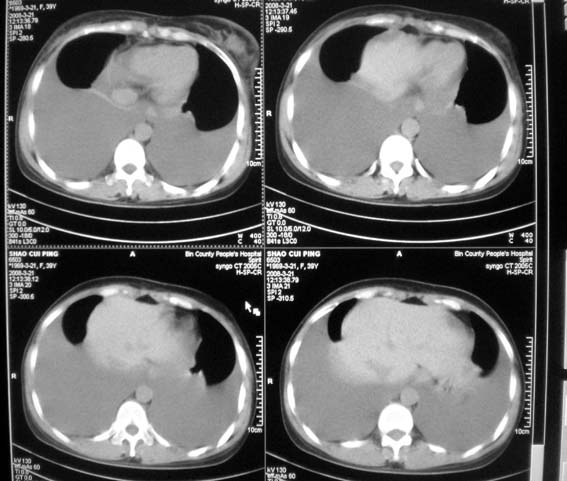

以下是引用zsl6918在2008-3-21 21:41:00的发言:[br]胸腔积液,心包积液,明确性质有难度。常规思路考虑结核性,建议抽液化验明确。

以下是引用卜一在2008-3-22 1:48:00的发言:[br][br] [br] 大量胸腔积液伴肺组织膨胀不全+心包积液。建议行纤支镜! [br] [br]

以下是引用随光逐影在2008-3-21 23:13:00的发言:[br]1)右肺中叶及左肺上叶舌段感染性病变。2)右肺中叶周围型肺癌待排。3)双侧胸腔积液并双下肺部分肺组织膨胀不全。4)心包积液。

以下是引用拾荒者在2008-3-22 21:21:00的发言:[br]胸腔积液、心包积液,双下肺膨胀不全,建议穿刺细胞学检查或抽液后进一步ct检查。